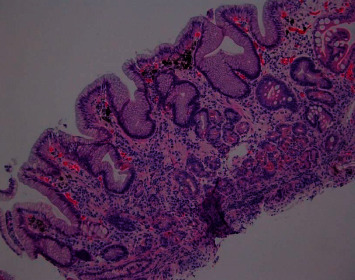

胃假性黑素病是一种良性疾病,其特征是胃壁内上皮下巨噬细胞内的色素沉积。这种情况的发生是罕见的,假性黑色素病更常发生在十二指肠黏膜。胃粘膜内的假性黑色素瘤病例很少报道。我们报告一个病例86岁的女性谁提出了恶化缺铁性贫血有关胃肠道出血。她的内镜检查显示胃内有斑点状的深色色素沉着,经组织学检查证实为假性黑色素病,色素铁染色呈阳性。

Gastric pseudomelanosis is a benign condition that has been characterized by pigment deposition within subepithelial macrophages inside the stomach wall. Occurrence of the condition is rare, with pseudomelanosis occurring more often within the duodenal mucosa. Few cases have reported pseudomelanosis within the gastric mucosa. We report a case of an 86-year-old female who presented with worsening iron deficiency anemia concerning for gastrointestinal bleeding. Her endoscopic evaluation was remarkable for a speckled pattern of dark pigmentation within the stomach, confirmed to be pseudomelanosis by histologic evaluation with pigment showing positive staining for iron.